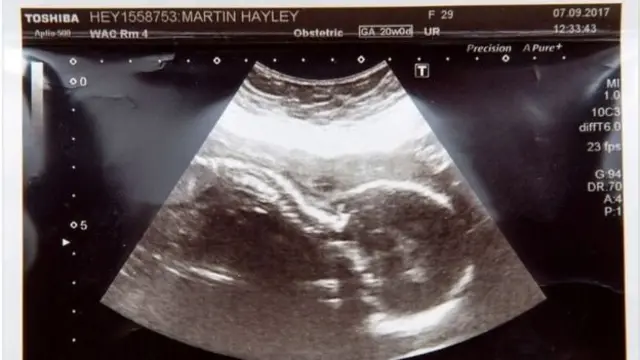

На 20 тижні вагітності лікарі повідомили Гейлі Мартін, що в її дитини рідкісне вроджене захворювання - двостороння агенезія нирок. Маля може народитися мертвим або загинути через кілька хвилин після народження.